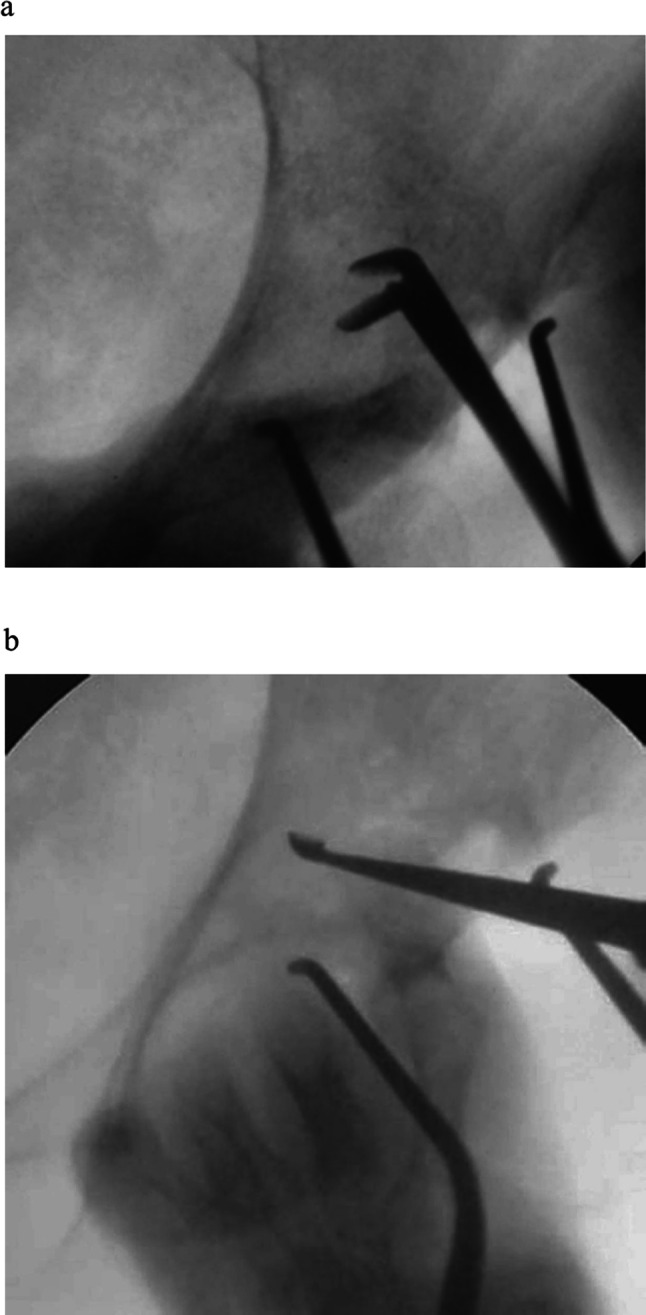

Bone metastasis in the periacetabular region usually causes severe pain and functional disability. Some surgical procedures, such as the Harrington surgery and percutaneous cementoplasty, have been reported as treatment options for periacetabular bone metastases with limited efficacy. The former is highly invasive, while the latter may not allow the injection of a sufficient amount of cement. Here we report two surgical cases using a new modified surgical method (mini-open periacetabular cementoplasty: MO-PAC) consisting of tumor curettage and cementoplasty through a small incision.

髋臼周围骨转移通常引起剧烈疼痛和功能障碍。一些外科手术,如Harrington手术和经皮骨水泥成形术,已被报道为髋臼周围骨转移的治疗选择,但疗效有限。前者是高度侵入性的,而后者可能不允许注入足够数量的水泥。在此,我们报告了两例手术病例,采用了一种新的改良手术方法(迷你开放髋臼周围骨水泥成形术:MO-PAC),包括肿瘤刮除和小切口骨水泥成形术。